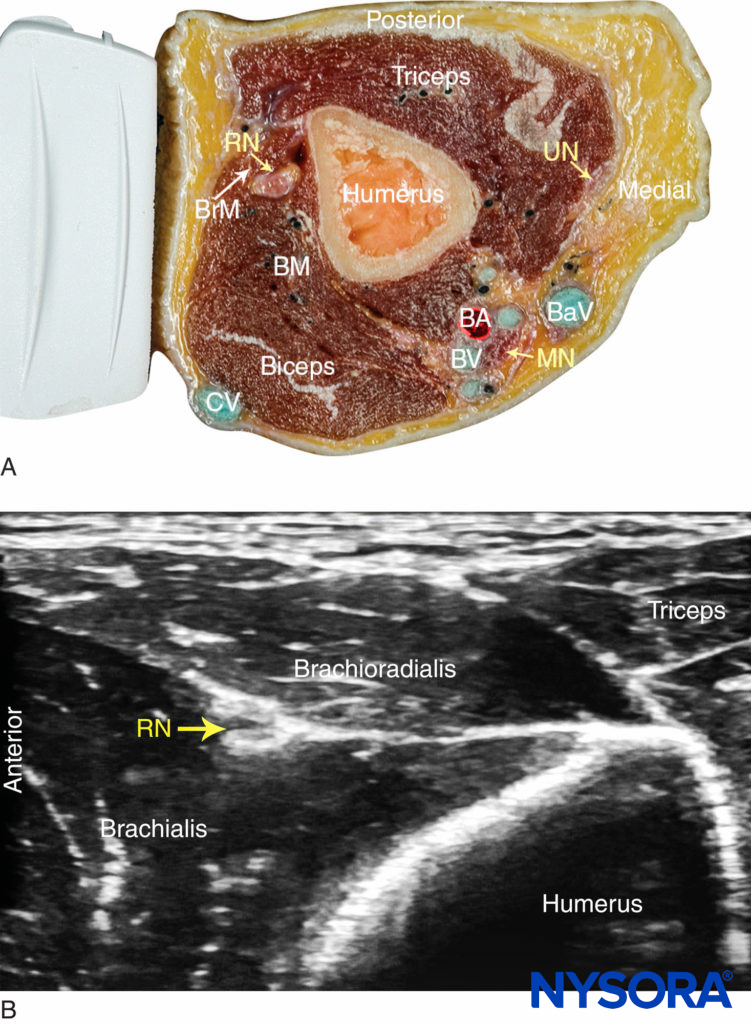

The radial nerve is best visualized above the lateral aspect of the elbow, lying in the interfascial plane between the brachioradialis and the brachialis muscles (Figure 2). The transducer is placed transversely on the anterolateral aspect of the distal arm, 3–4 cm above the elbow crease. The nerve appears as a hyperechoic, triangular or oval structure with the characteristic honeycomb appearance of a distal peripheral nerve. The nerve divides just distal to the elbow crease into the superficial (sensory) and deep (motor) branches. These smaller divisions of the radial nerve are more challenging to identify in the forearm; therefore, a single injection above the elbow is favored because it ensures block of both. The transducer can slide up and down the arm to better visualize the nerve and the musculature surrounding it. As the transducer is moved proximally, the nerve will be seen to travel posteriorly and closer to the humerus, to lie deep to the triceps muscle in the spiral groove (Figure 3).

FIGURE 2. (A) Radial nerve (RN) anatomy at the distal third of the humerus. BrM, brachioradialis muscle; BM, brachialis muscle; BA, brachial artery; BV, brachial vein, BaV, basilic vein, CV, cephalic vein; UN, ulnar nerve; MN, median nerve. (B) Sonoanatomy of the radial nerve at the distal arm. The RN is located between the brachioradialis and the brachialis muscles.

FIGURE 3. Sonoanatomy of the radial nerve (RN) in the spiral groove of the humerus. PAbCN, posterior antebrachial cutaneous nerve.